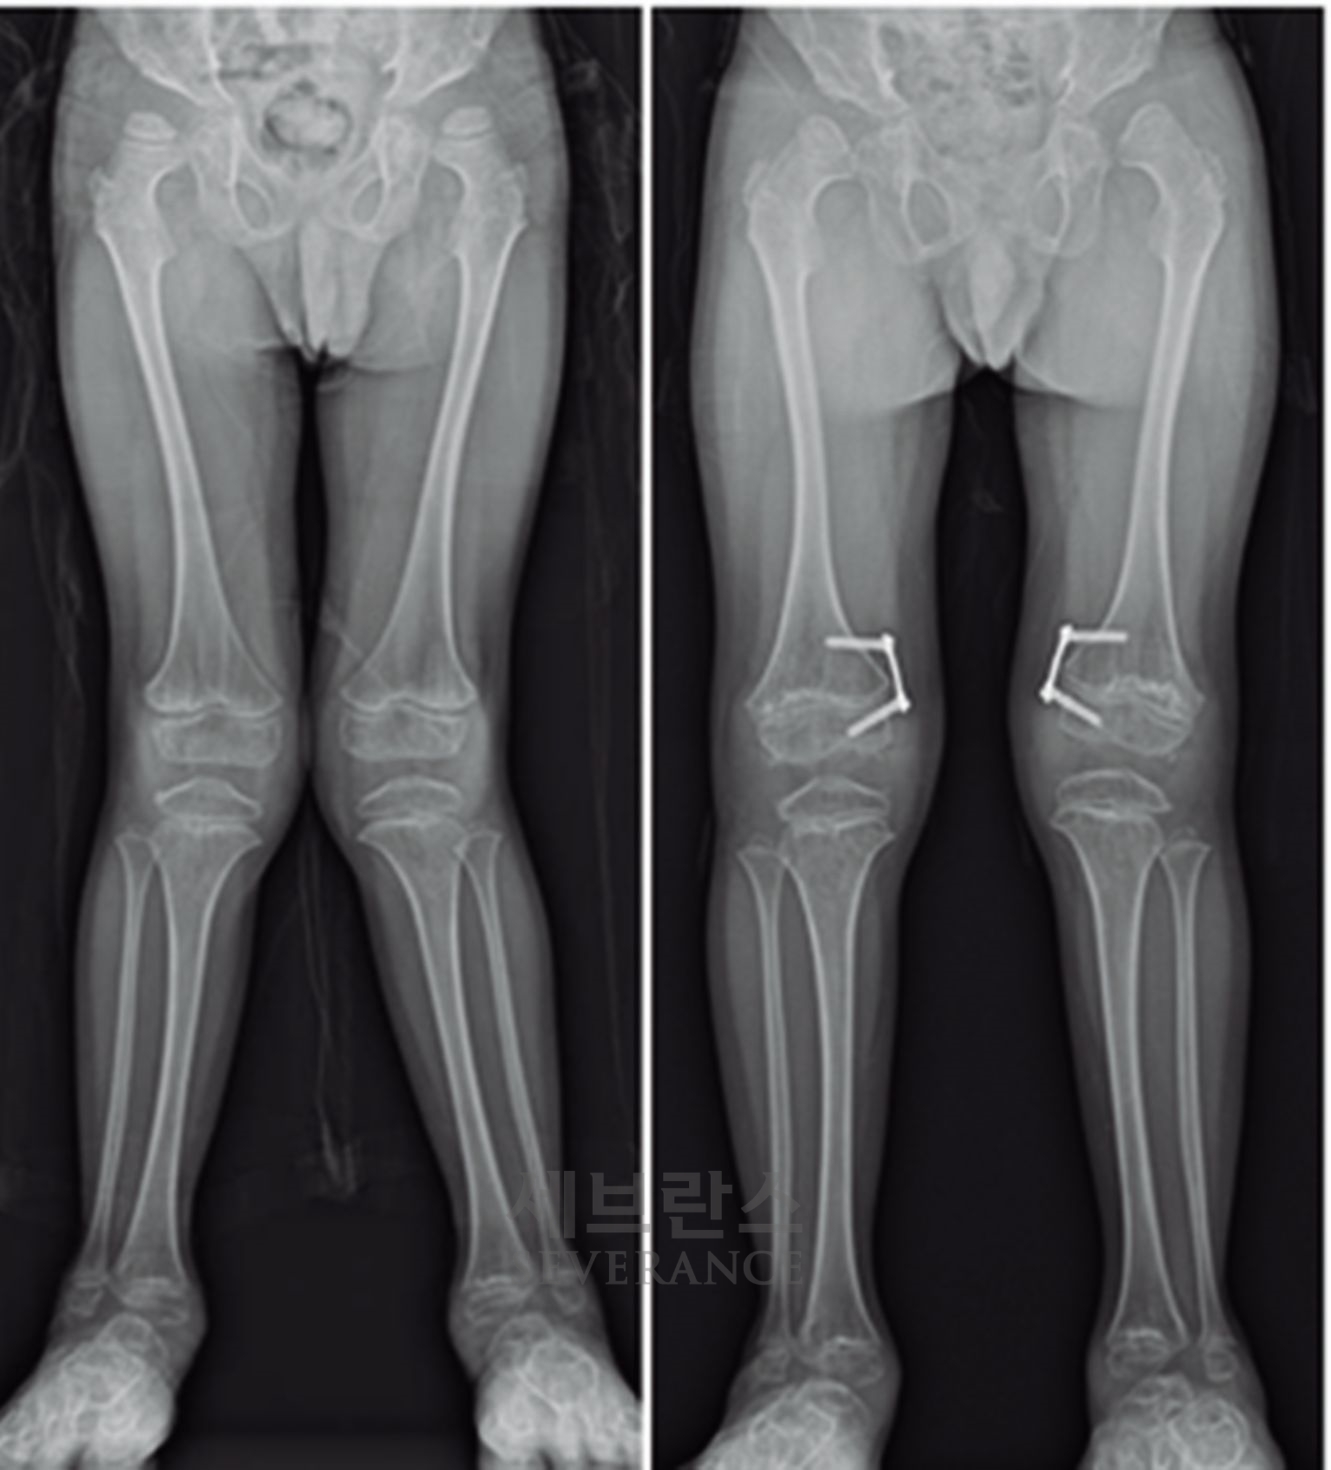

특발성 대사성 질환으로 인한 외반슬(X다리)에서 성장조절술을 시행한 환아성장판